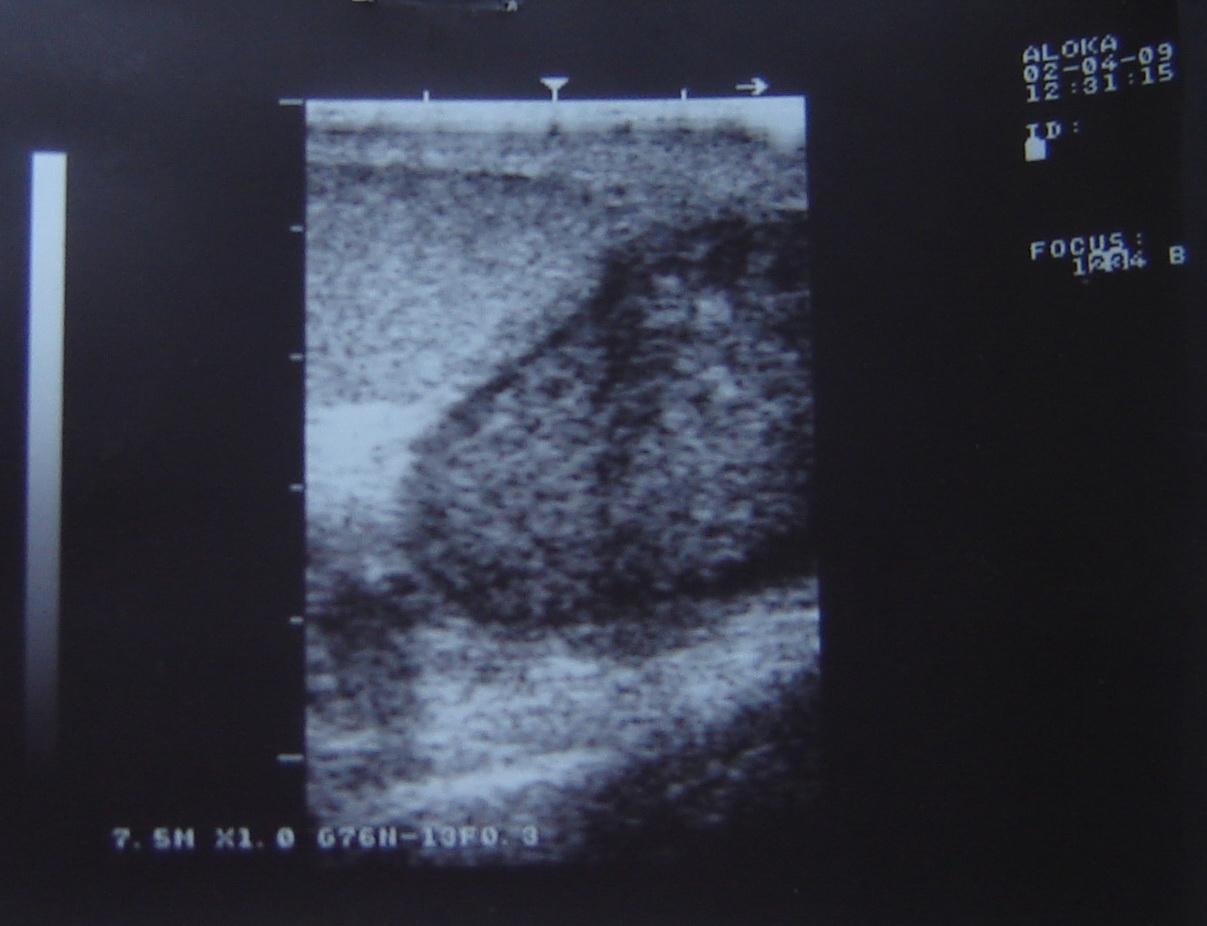

Уважаемый Алексей! По одному УЗИ не ставится диагноз. Надо сдать кровь на альфа-фетопротетеин и хореонический гонадотропин, сделать доппрерографию яичка. Проявите онконастороженность. Все лечится, если вовремя выявить. Напишите нам о результатах обследования.